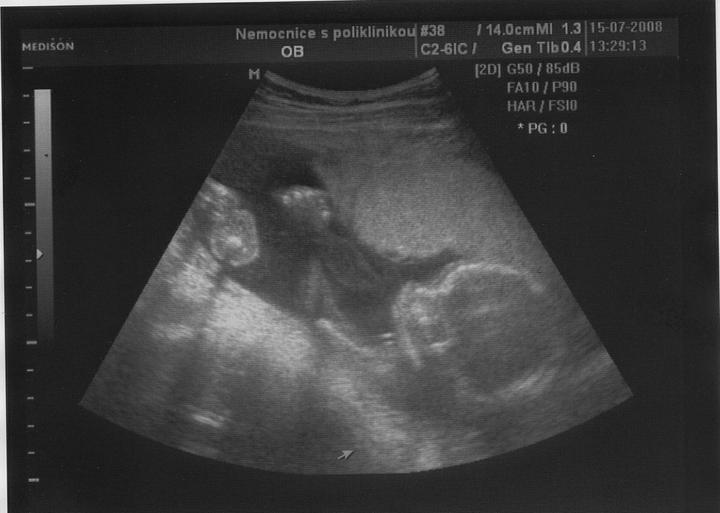

Doktor mi začátkem listopadu 2007 vysadil HA z důvodu zdravotních potíží,dávali jsme si tedy pozor a čekali,zda potíže ustoupí,ale 31.prosince 2007 mi manža řekl,že by chtěl miminko,byla jsem z jeho návrhu vykulená,ale byla to překrásná představa a tak jsem souhlasila..Od 8.ledna 2008 jsme se tedy začali snažit o miminko,začala jsem pít kontryhel a zobat Calibrum babyplan,aby mému tělu nic nechybělo 🙂 Nechávali jsme tomu volný průběh,ani jeden z nás na to nijak nepospíchal,nevím,proč jsem si říkala : Do roka se to snad povede 😀 A 29.3.2008 jsem měla pozitivní testík,sama jsem nechápala,jak brzy se to povedlo 🙂 Byla jsem neskutečně šťastná a stále jsem 🙂 Termín porodu dle MS 5.12.2008 a dle utz ve 12.tt 30.11.2008 Už od začátku jsem tušila,že čekám kluka a tak hned z první kontroly v 5.tt jsem si koupila modré bačkůrky pro štěstí,které se mnou chodili na každou kontrolu 🙂 Od 15.tt mi začalo celkem hodně tvrdnout břicho a chvilkama to bylo velice nepříjemné,na další kontrole,to jsem byla 18+4 , jsem to doktorovi řekla,ten mi pověděl,že se mu to vůbec nelíbí a tak mě poslal na utz,na utz jsem čekala 2 hodiny a můžu říct,že to byli nejhorší 2 hodiny v mém životě,tolik jsem se o miminko bála,ten strach,že něco není v pořádku byl opravdu k nevydržení..Přišla na mě řada a tak jsem tedy šla do kabinky a následně na lehátko na utz,pan doktor konstatoval,že všechno vypadá v pořádku a že se nemám bát,předepsal mi magnezium a že by to mělo pomoct,navíc koukám na ten utz a povídám panu doktorovi,to co tam vidím jsou kouličky? 😀 A on že jistě,že si myslel,že už to dávno vim,když se tak krásně ukazuje 😀 ,můj doktor mi řekl,že zřejmě porodím předčasně,což mě celkem vyvedlo z míry..Ale jsem optimisticky naladěnej človíček a tak jsem Honzíkovi vysvětlovala,že v bříšku musí ještě zůstat..Ve 20.tt jsem šla na velkej UTZ,kde mi opravdu řekli,že Honzík je zdravej a opět Honzík ukázal,že je 100% chlapeček 😀 Ve 26.tt jsme jeli na 4D utz do Liberce,tam se Honzík ukázal zas,no za celé těhu se nestalo,že by se na utz neukázal aa neroztáhl nožičky,máme malýho exibouše 😀 Ve 30.tt mě čekal další UTZ,vše v pořádku,Honzík už byl hlavičkou dolů a vážil 1600g ..Ve 35.tt mě doktor opět kvůli tvrdnutí břicha poslal už do ambulance,aby se o mě starali už tam.. Ten den jsem strávila v nemocnici 7hodin,fakt děsný !!! 2 hodiny čekání u mého doktora,ten mě tedy poslal už do nemocnice,takže jsem musela na UTZ,tam jsem čekala 2 hodiny,pak na natáčky,tam jsem čekala hodinu a pak na ambulanci a tak jsem čekala zas dvě hodiny ☹ Na UTZ ve 36.tt měl Honzík už 2600g ..